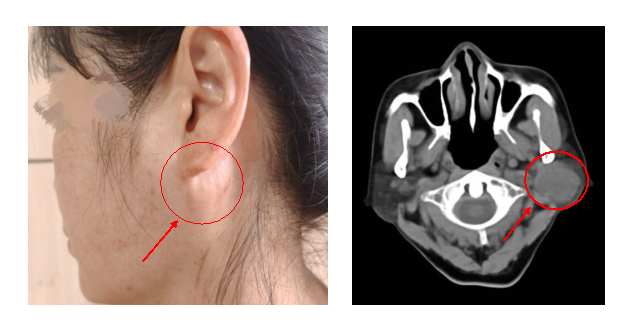

三个月前,陈奶奶因突发主动脉夹层植入了血管支架,需长期服用抗凝药物。而两年前她左侧耳后出现的包块,已长至「鸡蛋」大小,半月前被确诊为「腮腺肿瘤」。由于支架术后出血风险极高,多家医院评估后均认为手术风险过高「不敢动刀」。面对肿瘤逐渐增大与健康威胁的双重压力,陈奶奶焦急万分,最终来到中南医院口腔医学中心寻求救治。

经过充分准备,2025 年 6 月 4 日,口腔颌面外科程波主任医师团队在全麻下为陈奶奶实施了「左侧腮腺肿瘤切除术」。术中,肿瘤与面神经紧密粘连,分离过程稍有不慎就可能损伤神经导致面瘫。程波主任凭借丰富经验与精细操作,历时 3 小时,最终完整切除肿瘤,并成功保留了所有面神经分支功能。目前,陈奶奶恢复良好,无面瘫及出血并发症。